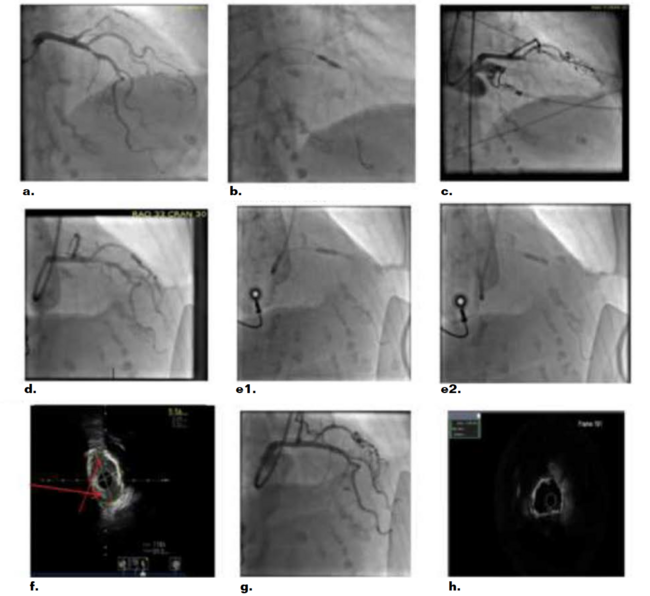

A 93-year-old female with hypertension and chronic kidney disease presented with dyspnea, elevated high-sensitivity troponin at 210 ng/L, and nonspecific electrocardiogram changes consistent with non-STEMI (NSTEMI). Echocardiogram showed an ejection fraction (EF) of 45% with anterolateral and inferior wall motion abnormalities. After detailed discussion of the risks and benefits of heart catheterization, an early invasive strategy was planned. Aspirin (324 mg) was administered and intravenous heparin started. Right radial access was obtained, and a coronary angiogram was performed using 6 Fr catheters. Coronary angiography showed a culprit proximal left circumflex 99% stenosis successfully treated with a 2.25-mm x 24-mm Synergy drug-eluting stent (DES) (Boston Scientific). The mid left anterior descending (LAD) artery had a 90% lesion (Figure 1a) that did not appear to be severely calcified. We initially used a 3.5-mm x 15-mm NC Emerge balloon (Boston Scientific) that crossed and inflated up to 12 ATM and then to high pressure at 20 ATM without successful dilation. Due to heavy calcification, there was a residual waist despite multiple balloon inflations (Figure 1b). Next, we escalated to scoring balloons, including a 3.0-mm Wolverine (Boston Scientific) and 2.5-mm AngioSculpt (Philips), neither of which crossed the lesion. We terminated the procedure with plans to bring the patient back to the lab for plaque modification with atherectomy of the LAD artery lesion. The patient was preloaded with 600 mg clopidogrel. The activated clotting time at that point was greater than 300 seconds. The radial sheath was removed without complication. Post procedure, while on the procedure table, the patient developed jaw pain and severe chest pain. EKG showed ST-segment elevation anteriorly. Emergently, access was obtained through the right common femoral artery, and coronary angiography demonstrated a total occlusion of the mid LAD and TIMI 0 (Figure 1c), likely secondary to plaque rupture and thrombotic occlusion,

A workhorse wire was advanced and crossed the lesion, and TIMI 3 flow was restored immediately consistent with transient thrombus. A compliant balloon (2.5 mm) was used with continued residual waist. There was evidence of edge dissection just proximal to the lesion (Figure 1d). The patient was started on a glycoprotein IIb/IIIa inhibitor (tirofiban). Atherectomy was contraindicated because of the risk of extending the dissection and the high chance for distal embolization with the presence of thrombus. A 3.5-mm x 12-mm Shockwave balloon was advanced as a last resort and was wedged into the proximal portion of the plaque. Three sets of 10 pulses were delivered with inflation to 4 ATM, and each time the balloon was advanced gradually into the lesion until total crossing of the lesion (Figure 1e1 and Figure 1e2). Following lithotripsy, the lesion was dilated with a 3.5-mm x 12-mm NC balloon at 12 ATM with full balloon expansion. Intravascular ultrasound (IVUS) post Shockwave lithotripsy showed fractured calcium in 2 different areas (Figure 1f) . A 3.5-mm x 24-mm Synergy stent was deployed and inflated up to 16 mm ATM, then post dilated with a 4.0 x 8 NC Emerge balloon at 16 ATM with no residual narrowing (Figure 1g). Post stent IVUS showed a minimal stent area of 9 mm2 (Figure 1h) with good opposition and expansion of the stent.